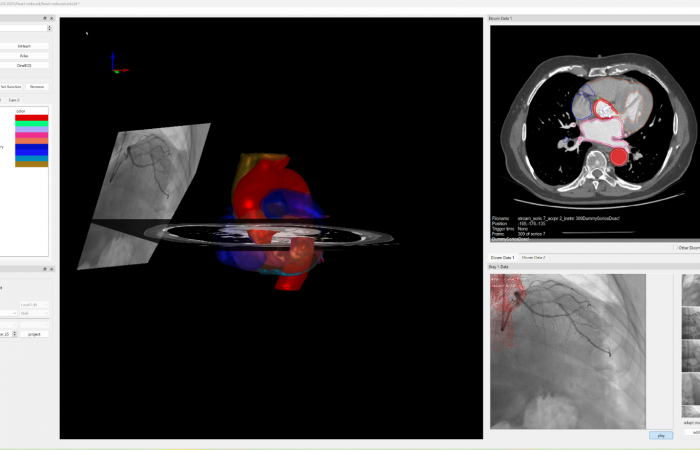

Pracownia Funkcjonalnego i Wirtualnego Medycznego Obrazowania 3D (Pracownia 3D-FM) funkcjonuje w strukturze Zakładu Diagnostyki Obrazowej Szpitala Uniwersyteckiego w Krakowie pod kierownictwem Prof. dr hab. Tadeusza Popieli. Jej celem jest opracowanie i wdrożenie innowacyjnych metod przetwarzania oraz analizy sygnałów i obrazów medycznych, w tym wykorzystanie technologii rzeczywistości wirtualnej oraz metod obrazowania funkcjonalnego. Rozwiązania te wspierają przedoperacyjne planowanie, monitorowanie procedur medycznych oraz wzbogacają proces diagnostyczny o nowe formy wizualizacji danych medycznych.

Pracownia 3D-FM zajmuje się m.in. następującymi obszarami:

- Tworzeniem modeli 3D do celów przedoperacyjnego planowania oraz wizualizacji diagnostycznej.

- Rozwojem rozwiązań programowych do obrazowania medycznego.

- Integracją urządzeń i systemów diagnostycznych (PACS, RIS, HIS, OIS) z infrastrukturą szpitalną, umożliwiającą efektywne zarządzanie danymi obrazowymi i funkcjonalnymi.

- Oceną jakości i poprawności danych medycznych w celach wizualizacji przestrzennych oraz optymalizacją protokołów akwizycji i konfiguracją urządzeń do tych celów.

- Obrazowanie funkcjonalne

- Elektrokardiograficzne obrazowanie 3D (ECGI)